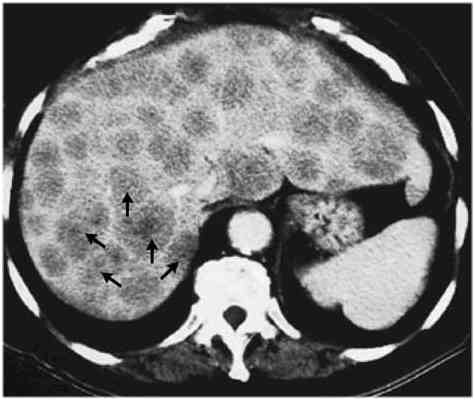

As noted in CT pictures, liver metastases may be multiple (picture on far left) or present with one large mass. The pattern would impact on how the liver could be best treated.

cross section through liver,    Primary liver cancers (hepatoma) can look like liver mets (go here).